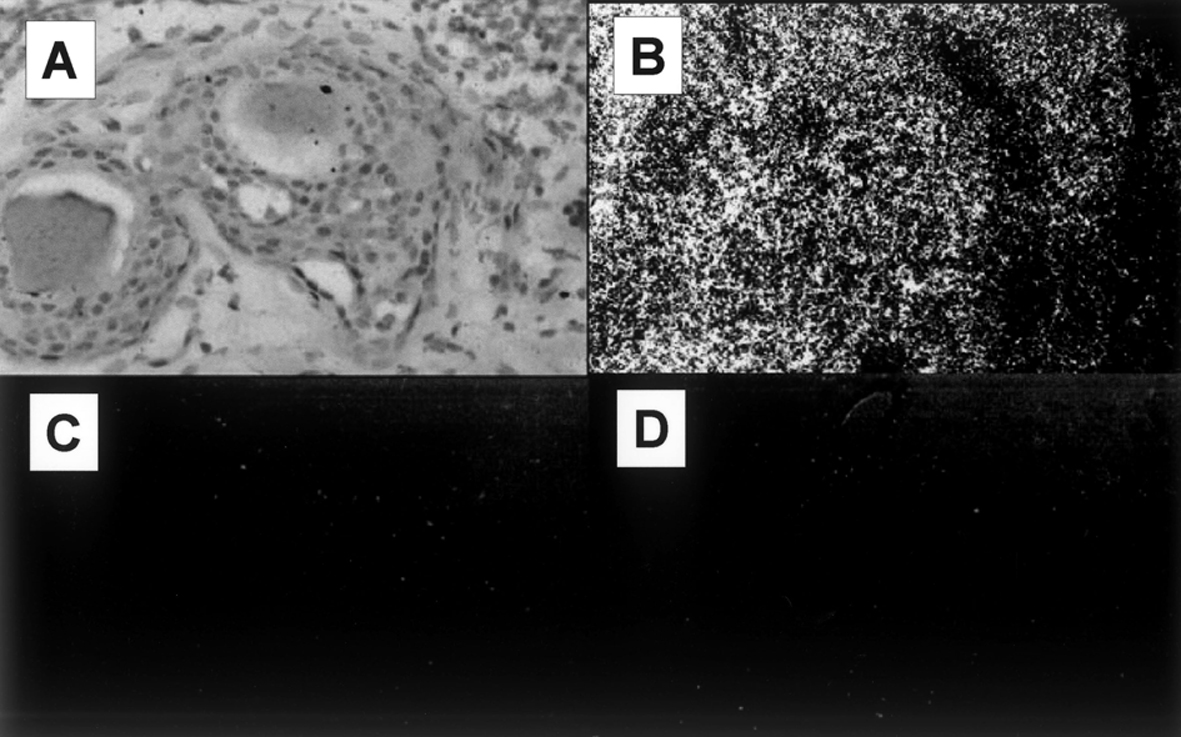

In the ISH using the antisense probe, DcR3 mRNA expression was found to be prominent in breast cancer cells. The signals were negligible in breast cancer cells and normal breast tissues tested with the sense probe or antisense probe. These results show that DcR3 mRNA is detectable in breast cancer cells by ISH (Fig. 1).

![]() Click for large image | Figure 1. DcR3 mRNA expression analysis by ISH. (A) Light microscopy of breast cancer cells. (B) DcR3 mRNA expression is prominent in breast cancer cells, as visualized with the antisense probe. (C) The signals for the sense probe are negligible in the breast cancer cells. (D) The signals for the antisense probe are negligible in the normal breast cells. |